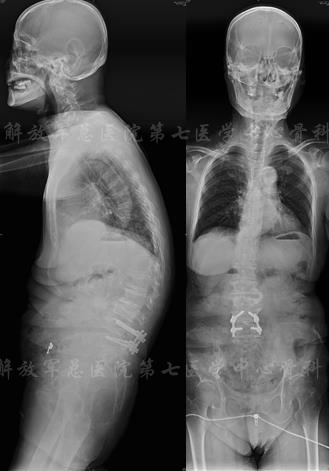

影像学检查

X线片

X线全长片:胸腰段Cobb角(L2-T11):25度;腰椎生理前凸:PI:53、PT:38、SS:15、LL:20;膝关节的屈曲畸形5度

影像学检查

X线片

颈部X线片

X线片:TL cobb 38、PI 53、SS 13、PT 40、LL 9